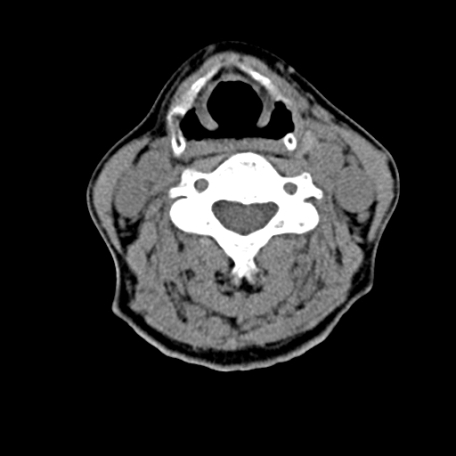

标题: CT24010:患者女56岁双侧甲状腺摘除术后一月复查,患者现感 [打印本页]

标题: CT24010:患者女56岁双侧甲状腺摘除术后一月复查,患者现感

甲状腺术后复发,现在甲状腺区域仍有密度不均匀之软组织密度影。

甲状腺区域密度不均匀密度影,应该是术后改变,要鉴别是否复发,建议增强检查。

“甲状腺摘除术后一月复查”,有病理吗?考虑术后复发,可能是恶性,颌下及左侧颈部淋巴结有肿大。

考虑术后复发,并颈部淋巴结肿大。请结合临床。

双侧甲状腺肿大,伴多发低密度灶(性质待定);建议行进一步检查。

双侧甲状腺肿大,周围结构不清,术后复发时间有点短,考虑出血并感染。